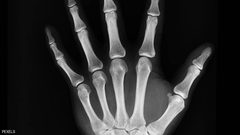

كيف تحمي عظامك مع تقدمك في العمر